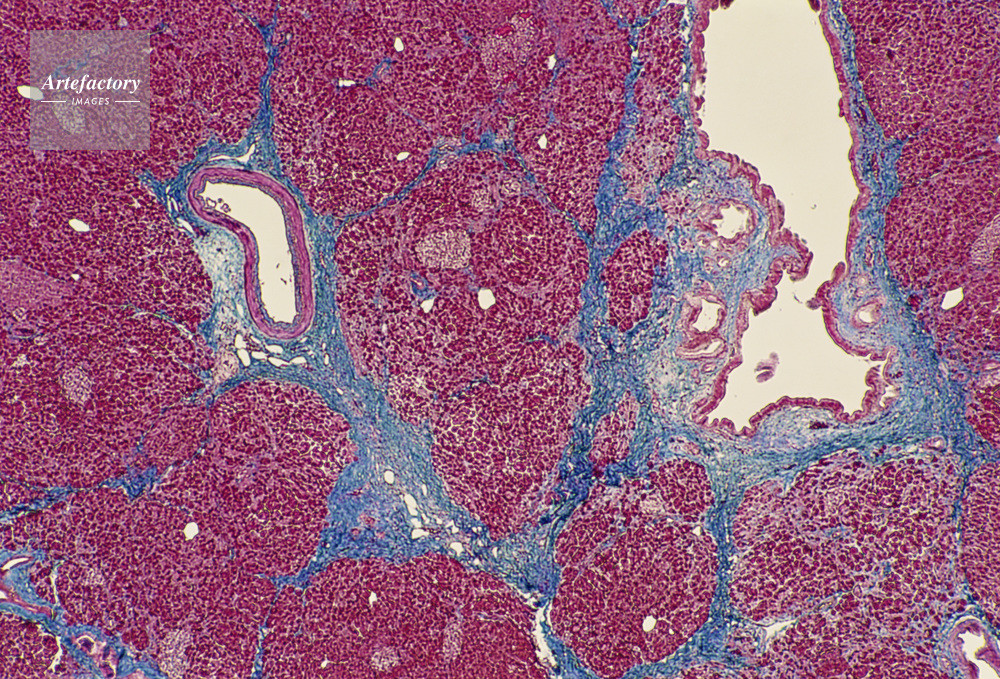

| キャプション | 脾臓,人間,20倍 | 制限事項 | ||